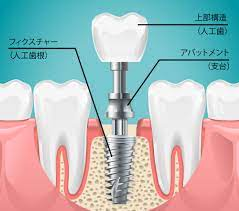

インプラントとは

失われた歯の代わりとなる物。チタンでできていて、入れ歯やブリッジと違い骨に直接結びつくため、自分の歯と同じようにつかうことができます。

治療方針が決まると、詳しい検査やレントゲン撮影(CT)が行われます。さらに口腔内模型の採取もします。このデータをもとにインプラントの埋入方向や深度、インプラントの太さなどを決めていきます。